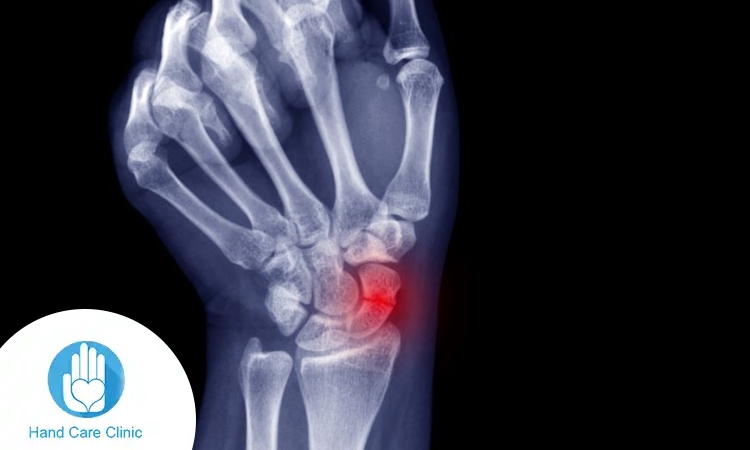

يشير مصطلح كسر الزورقيه إلى حدوث شرخ أو كسر في عظمة الزورقية، وهي إحدى العظام الصغيرة داخل مفصل الرسغ وتقع تحديدًا في المنطقة القريبة من قاعدة الإبهام. ورغم صغر حجمها، فإن هذه العظمة تلعب دورًا مهمًا في الربط بين صف العظام القريبة من الساعد وبقية عظام اليد، مما يجعلها عنصرًا أساسيًا في تحقيق التوازن بين ثبات الرسغ ومرونته أثناء الحركة.

تكمن أهمية فهم طبيعة كسر الزورقيه في أن مكان الكسر ودرجة شدته يؤثران بشكل مباشر على خطة العلاج ومدة الشفاء. وتتميز هذه العظمة بخصوصية طبية مهمة، وهي أن إمدادها الدموي محدود نسبيًا، خاصة في بعض أجزائها، مما يجعل عملية الالتئام أبطأ مقارنة بكسور أخرى في الجسم، ويزيد الحاجة إلى التشخيص المبكر والالتزام بالعلاج.

- بطء الالتئام بسبب ضعف التروية الدموية: محدودية وصول الدم إلى أجزاء من العظمة قد تؤدي إلى تأخر الشفاء أو عدم الالتئام في بعض الحالات إذا لم يتم العلاج بشكل صحيح.